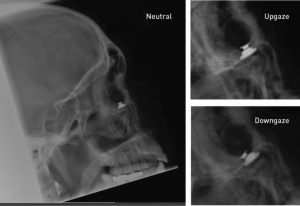

A case of a pilot, experimental intervention using magnetic oculomotor prosthesis has also been reported with objective improvement of visual acuity and reduction of acquired nystagmus.[79] (See Figure 8.)